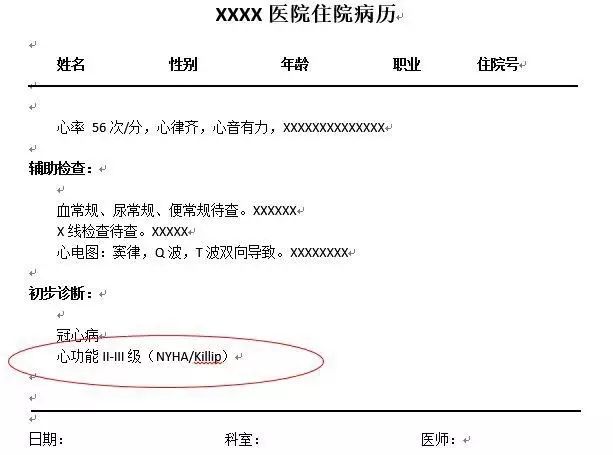

你知道病历和化验单上的结果都有哪些含义吗?

♥NYHA分级(纽约心功能分级):用来评价心功能受损的程度。按照诱发心衰的活动程度把心功能的受损状况分为四个等级,I级最轻,IV级最严重。NYHA分级帮助心衰患者和医生简易地了解心功能受损和病情严重程度,可以帮助选择合适的检查、治疗方案。